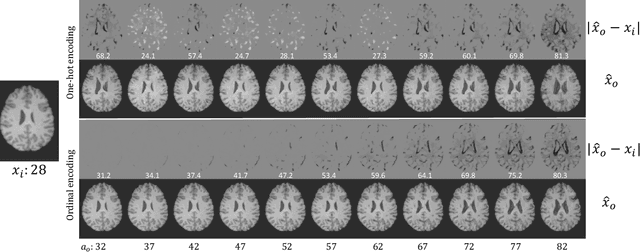

Abstract:Brain ageing is a continuous process that is affected by many factors including neurodegenerative diseases. Understanding this process is of great value for both neuroscience research and clinical applications. However, revealing underlying mechanisms is challenging due to the lack of longitudinal data. In this paper, we propose a deep learning-based method that learns to simulate subject-specific brain ageing trajectories without relying on longitudinal data. Our method synthesises aged images using a network conditioned on two clinical variables: age as a continuous variable, and health state, i.e. status of Alzheimer's Disease (AD) for this work, as an ordinal variable. We adopt an adversarial loss to learn the joint distribution of brain appearance and clinical variables and define reconstruction losses that help preserve subject identity. To demonstrate our model, we compare with several approaches using two widely used datasets: Cam-CAN and ADNI. We use ground-truth longitudinal data from ADNI to evaluate the quality of synthesised images. A pre-trained age predictor, which estimates the apparent age of a brain image, is used to assess age accuracy. In addition, we show that we can train the model on Cam-CAN data and evaluate on the longitudinal data from ADNI, indicating the generalisation power of our approach. Both qualitative and quantitative results show that our method can progressively simulate the ageing process by synthesising realistic brain images. The code will be made publicly available at: https://github.com/xiat0616/BrainAgeing.